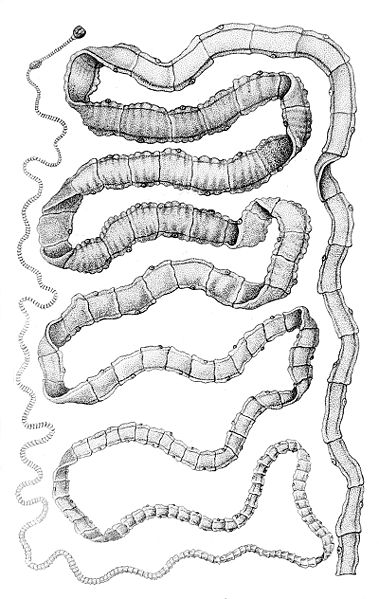

3. Sán dây

Còn được gọi với cái tên Taenia, loài giun hình dải ruy băng này có thể khiến bạn bị co giật nếu nó hình thành các u nang bên trong não của bạn. Tuy nhiên, nơi định cư phổ biến nhất của chúng là ở trong ruột của con người (hoặc vật nuôi).

Ấu trùng Taenia Solium có thể xâm nhập vào bên trong cơ thể một người khi người đó uống nước bị ô nhiễm hoặc ăn thịt lợn, thịt bò chưa nấu chín có chứa nang hoặc trứng sán dây.

Không phải mọi người nhiễm sán dây đều bị co giật, nó chỉ xảy ra khi ấu trùng Taenia ảnh hưởng đến hệ thần kinh trung ương ở người. Trong những trường hợp này, hầu như không thể chẩn đoán hoặc điều trị nhiễm sán dây vì bệnh nhân không có bất kỳ triệu chứng nào. Thông thường, loài này sẽ ảnh hưởng đến ruột non và gây táo bón, tiêu chảy, đau bụng,… Trong trường hợp nặng hơn, có thể dẫn đến động kinh, mù mắt, viêm màng não và nhiều vấn đề thần kinh khác. Sán dây là nguyên nhân của 30% các trường hợp động kinh ở nhiều vùng lưu hành dịch bệnh nơi người và lợn thả rong sống gần nhau.

Sán dây cũng là một trong những loại ký sinh trùng nguy hiểm phổ biến. Người ta ước tính rằng 5% người Mỹ có sán dây, nhưng hầu hết không nhận thức được điều này.